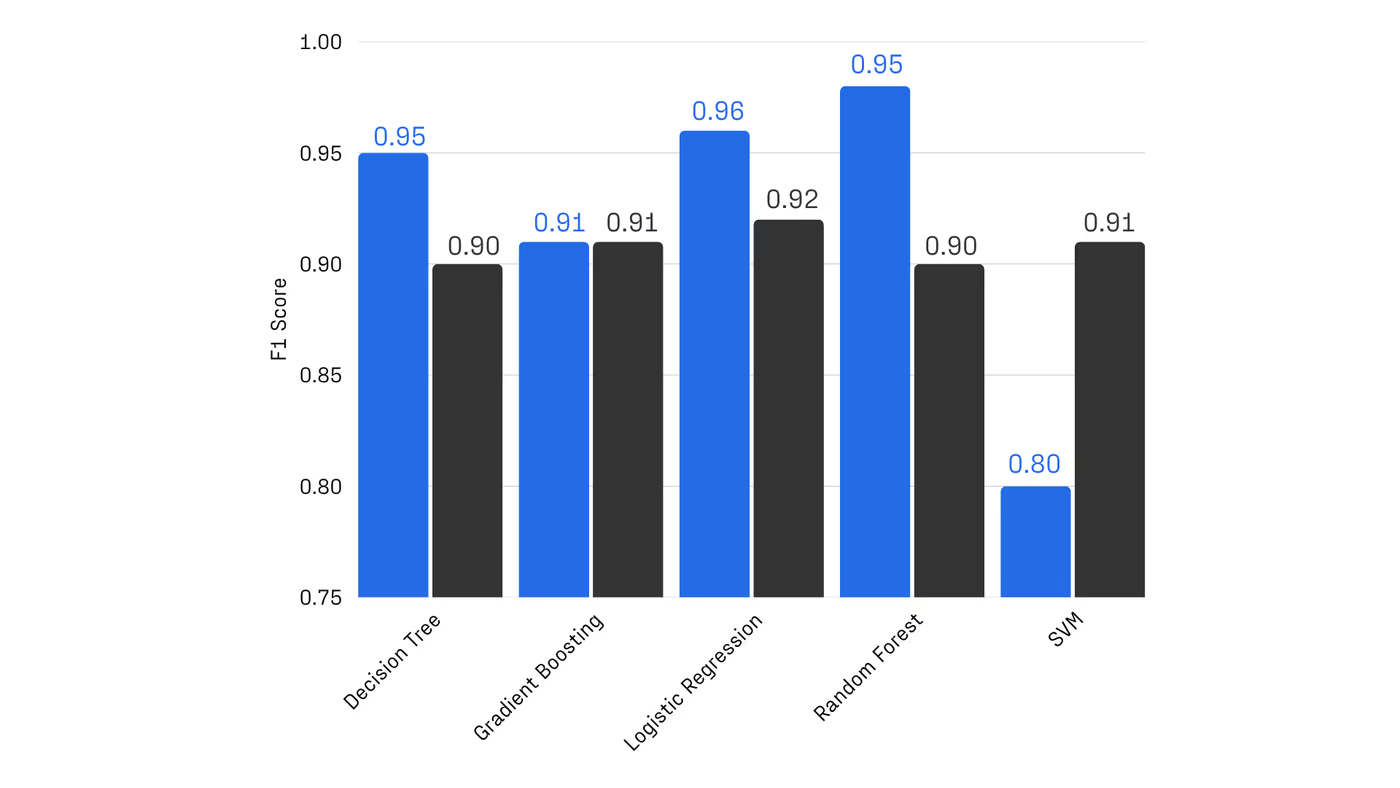

With R&D costs exceeding $2B per drug, pharma increasingly combines machine learning and computational chemistry to accelerate discovery. A powerful approach uses first-principles calculations to generate “quantum fingerprints”—physically grounded features that improve reactivity prediction. However, classical simulation methods scale poorly: they rely on approximations that are either too inaccurate to capture critical many-body effects or too expensive for practical screening.

Quantum computing offers a solution, but until now has been constrained by hardware noise, limiting usable circuit depth to a few hundred two-qubit gates. Haiqu, working with Capgemini, IBM, and GSK, broke this barrier by demonstrating one of the largest electronic-structure Hamiltonian simulations ever run on real quantum hardware for covalent drug warheads. Using advanced circuit compression and middleware execution, the team initially reduced circuit depth by 15.5× and further allowed end-to-end execution by running sub-circuits up to 371 gates.

Collectively, these results establish a scalable, hardware-realistic path for running Hamiltonian simulations on larger active spaces, while maintaining sufficient accuracy for molecular reactivity prediction.